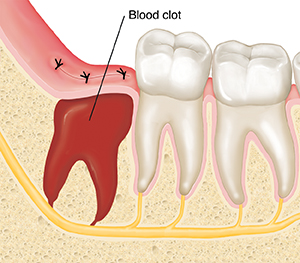

Healing after wisdom teeth removal usually takes a few months. First, a blood clot forms in the socket where the wisdom tooth was removed. This blood clot needs to stay in place to protect the bone and nerves. Within a day or two, the socket starts filling with repair tissue. This lays the foundation for new bone tissue to grow. When new bone tissue fills the socket, healing is complete.

| A few hours after surgery, a blood clot develops to fill the socket. |